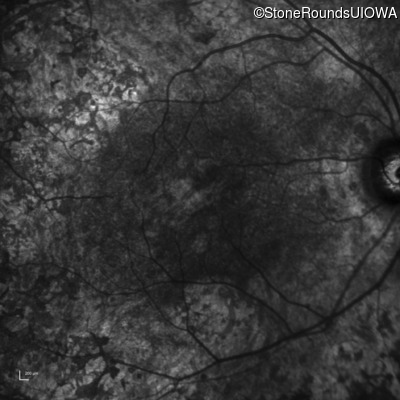

Infrared Fundus Photograph - Right - 20/150

Exemplar